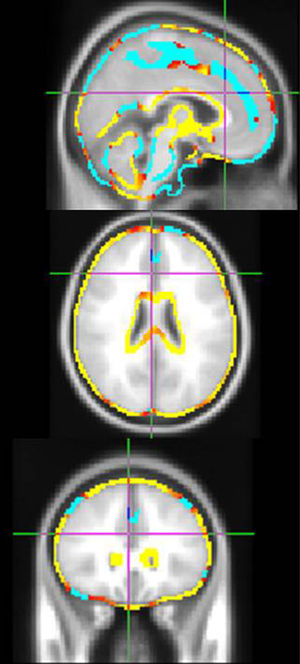

ResultsWe included 45 patients, of whom 25 were women. Mean follow-up time was 7.3±0.2 years. There were no sex-related differences in age at onset, follow-up time, and treatment (Table 1). The first MRIs revealed no sex-related differences in TBV, GMV, WMV and LV (Table 2). After 6 years, we observed no differences on the EDSS, multiple sclerosis severity score (MSSS), or WMV. However, men presented a significantly sharper decrease in TBV (P=.002) and GMV (P≤.001) and a significantly larger increase in LV (P=.02) and gAR (P<.001) than women (Table 3). Regarding regional atrophy, women presented more marked subcortical frontal atrophy than men, who in turn exhibited significantly greater global atrophy (Fig. 1).

Comparison of cerebral atrophy between men and women. Areas of atrophy more typically seen in women in the longitudinal follow-up are shown in blue, while atrophic areas more typically seen in men are shown in yellow/red. These colours can only be seen in the online version of this article.

In conclusion, our study demonstrates the presence of sex-related structural changes over the course of the disease. Men present greater global atrophy of cortical grey matter than women, who in turn experience more severe subcortical frontal impairment.